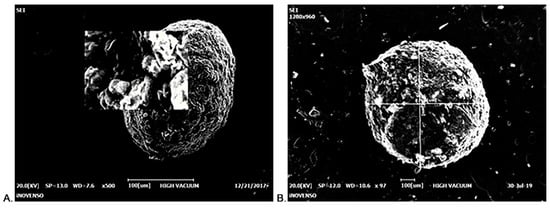

2.3. Morphological Characterization of CS-Gli-Sil Microparticles

3.1. CS-Gli-Sil Microparticles’ Synthesis